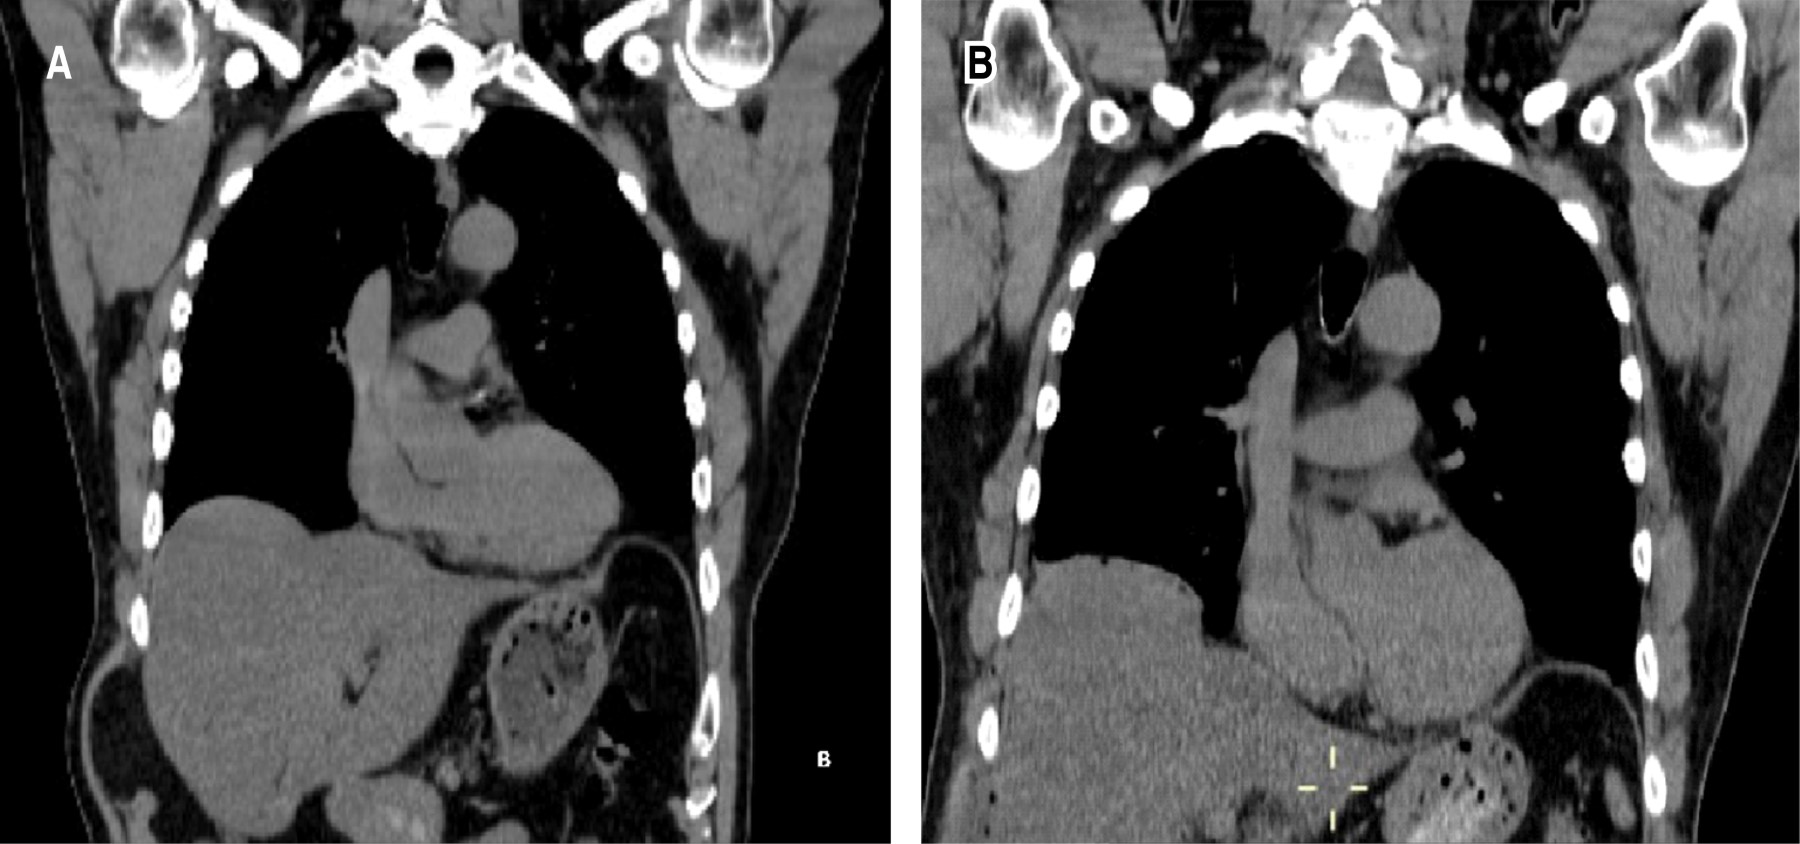

Thoraco-laparoscopic management of an acquired abdominal intercostal hernia

Abdominal intercostal hernias are a rare condition, characterized by the protrusion of the content of a hernia through an intercostal defect without diaphragmatic abnormalities. Most occur in the context of trauma and associated rib fractures. We present the case of a patient whose hernia was only associated with a chronic cough without a costal fracture. We describe a different form with a mixed approach to abdominal and chest reinforcement for minimal invasion.

Figure 2

Figure 3